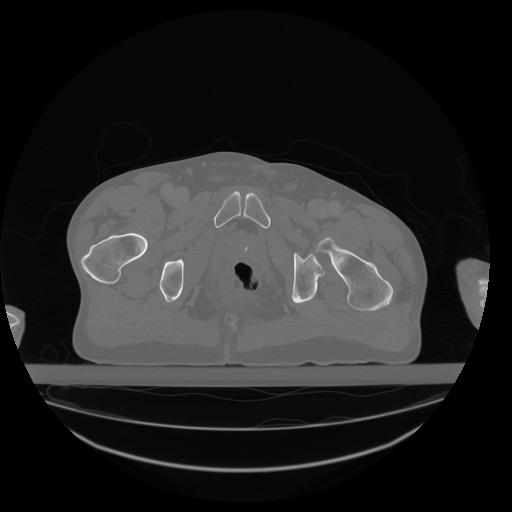

34 CUERPO,CE,Vol,1.0,CUERPO,,